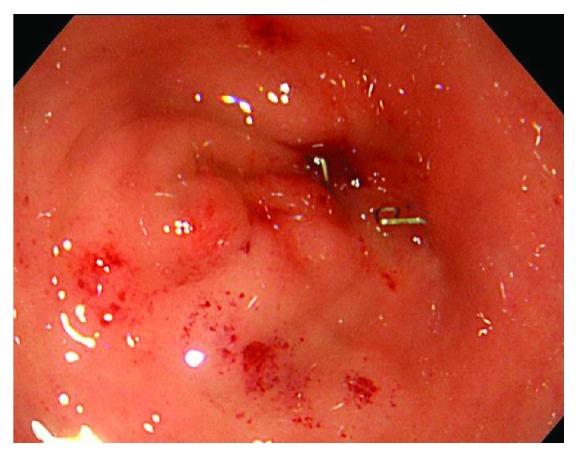

The double stapling technique has greatly facilitated intestinal reconstruction, particularly for anastomosis after anterior resection. However, anastomotic stenosis may occur, which sometimes requires surgical treatment. Redo surgery with reresection and reanastomosis presents a high risk of complications. Treatment methods need to be selected depending on the degree and location of stenosis. In an effort to propose a new resolution, reporting new cases and sharing valid experiences are necessary. An 82-year-old man diagnosed with rectal cancer had undergone laparoscopic anterior resection. Endoscopic balloon dilation performed for anastomotic stenosis had failed. Therefore, colostomy with double orifice was constructed on the oral side at 10 cm from the stenosis. Approaching from the anal and stoma side, the anastomotic stenosis was resected using a circular stapler. The colostomy was closed 1 month after surgery. Stenosis resection using a circular stapler requires the following steps: (1) passing the center shaft through the stenosis, (2) inserting the anvil head into the oral side of the stenosis, and (3) attaching the anvil head to the center shaft. This method can resect the stenosis using a circular stapler without being affected by postoperative adhesion in the pelvis. Compared to endoscopic balloon dilation, resection of the stricture by the circular stapler is thought to be reliable. This technique is particularly effective for localized stenosis, including anastomotic stenosis. It is considered that this method is minimally invasive and is low risk for complications. This method can contribute to the useful surgical option for refractory anastomotic stenosis after anterior resection.

双吻合器技术极大地促进了肠道重建,尤其是在前切除术后的吻合方面。然而,吻合口狭窄可能会发生,有时需要手术治疗。再次切除和重新吻合的再次手术并发症风险很高。治疗方法需要根据狭窄的程度和部位来选择。为了提出一种新的解决方案,报告新病例并分享有效经验是必要的。一名82岁被诊断为直肠癌的男性接受了腹腔镜前切除术。因吻合口狭窄进行的内镜球囊扩张失败。因此,在距狭窄处10 cm的口侧构建了双口结肠造口术。从肛门侧和造口侧进入,使用圆形吻合器切除吻合口狭窄。术后1个月关闭结肠造口。使用圆形吻合器切除狭窄需要以下步骤:(1)将中心轴穿过狭窄处,(2)将钉砧头插入狭窄处的口侧,(3)将钉砧头连接到中心轴上。这种方法可以使用圆形吻合器切除狭窄,而不受盆腔术后粘连的影响。与内镜球囊扩张相比,用圆形吻合器切除狭窄被认为更可靠。该技术对包括吻合口狭窄在内的局限性狭窄特别有效。认为这种方法微创且并发症风险低。这种方法可为前切除术后难治性吻合口狭窄提供有用的手术选择。